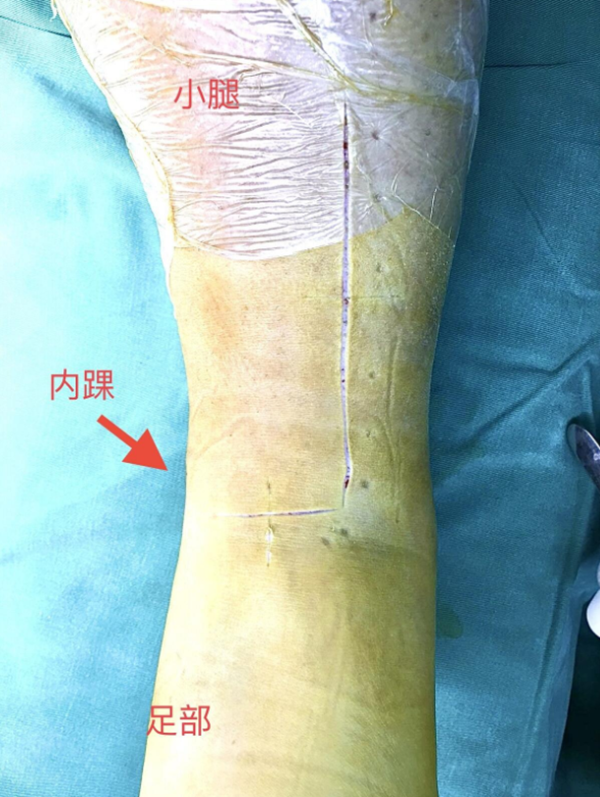

术中资料:切口与术中C-臂检测

图9 手术L切口远端横臂切口略偏近端,踝关节显露稍显不足,经延长“L”切口横臂后解决